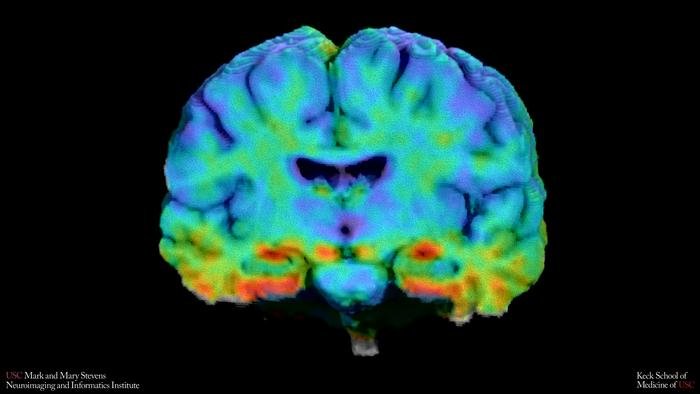

Researchers at the USC Mark and Mary Stevens Neuroimaging and Informatics Institute analysed tau PET brain scans from more than 1,500 older adults who were either cognitively normal or had mild cognitive impairment. Tau is a protein that forms tangles inside neurons, disrupting communication between brain cells; its accumulation in the medial temporal lobe, a region critical for memory, is considered one of the earliest warning signs of Alzheimer’s. Alongside tau, the team measured amyloid beta, the sticky plaques whose buildup typically precedes tau pathology in the standard model of disease progression.

Part of the explanation, the team found, might not be biological at all. The tau PET tracer used in the study can produce spurious signals from structures near the hippocampus, particularly the choroid plexus, a small tissue that produces cerebrospinal fluid. When the researchers statistically controlled for this off-target binding, the apparent tau differences in Black participants shrank considerably, though didn’t vanish entirely in the cognitively normal group. Hispanic participants continued to show significantly elevated tau even after adjustment, suggesting something real is driving those levels up. A similar problem affected lateral temporal regions, where Hispanic participants initially showed higher tau; but after a separate correction procedure removed signal leaking in from the brain’s outer membranes, that difference disappeared entirely. The finding is a methodological warning: if these imaging tools aren’t properly validated in diverse populations, apparent biological differences may be partially artefactual.